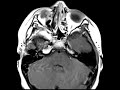

Neurofibromatosis Type 2

These images demonstrate bilateral small enhancing masses in the internal auditory canals compatible with vestibular schwannomas, a characteristic feature of Neurofibromatosis Type 2. In addition, there are enhancing masses in the right Meckel’s cave and left Cavernous sinus, both of which are likely additional schwannomas. In the spine, we see a cystic faintly enhancing lesion near the conus which most likely represents an ependymoma. NF-2 is also known as MISME or multiple inherited schwannomas, meningiomas, and ependymomas. The differential for isolated bilateral masses of the IACs should include metastasis in patient with a history of cancer or granulomatous diseases such as Sarcoidosis.